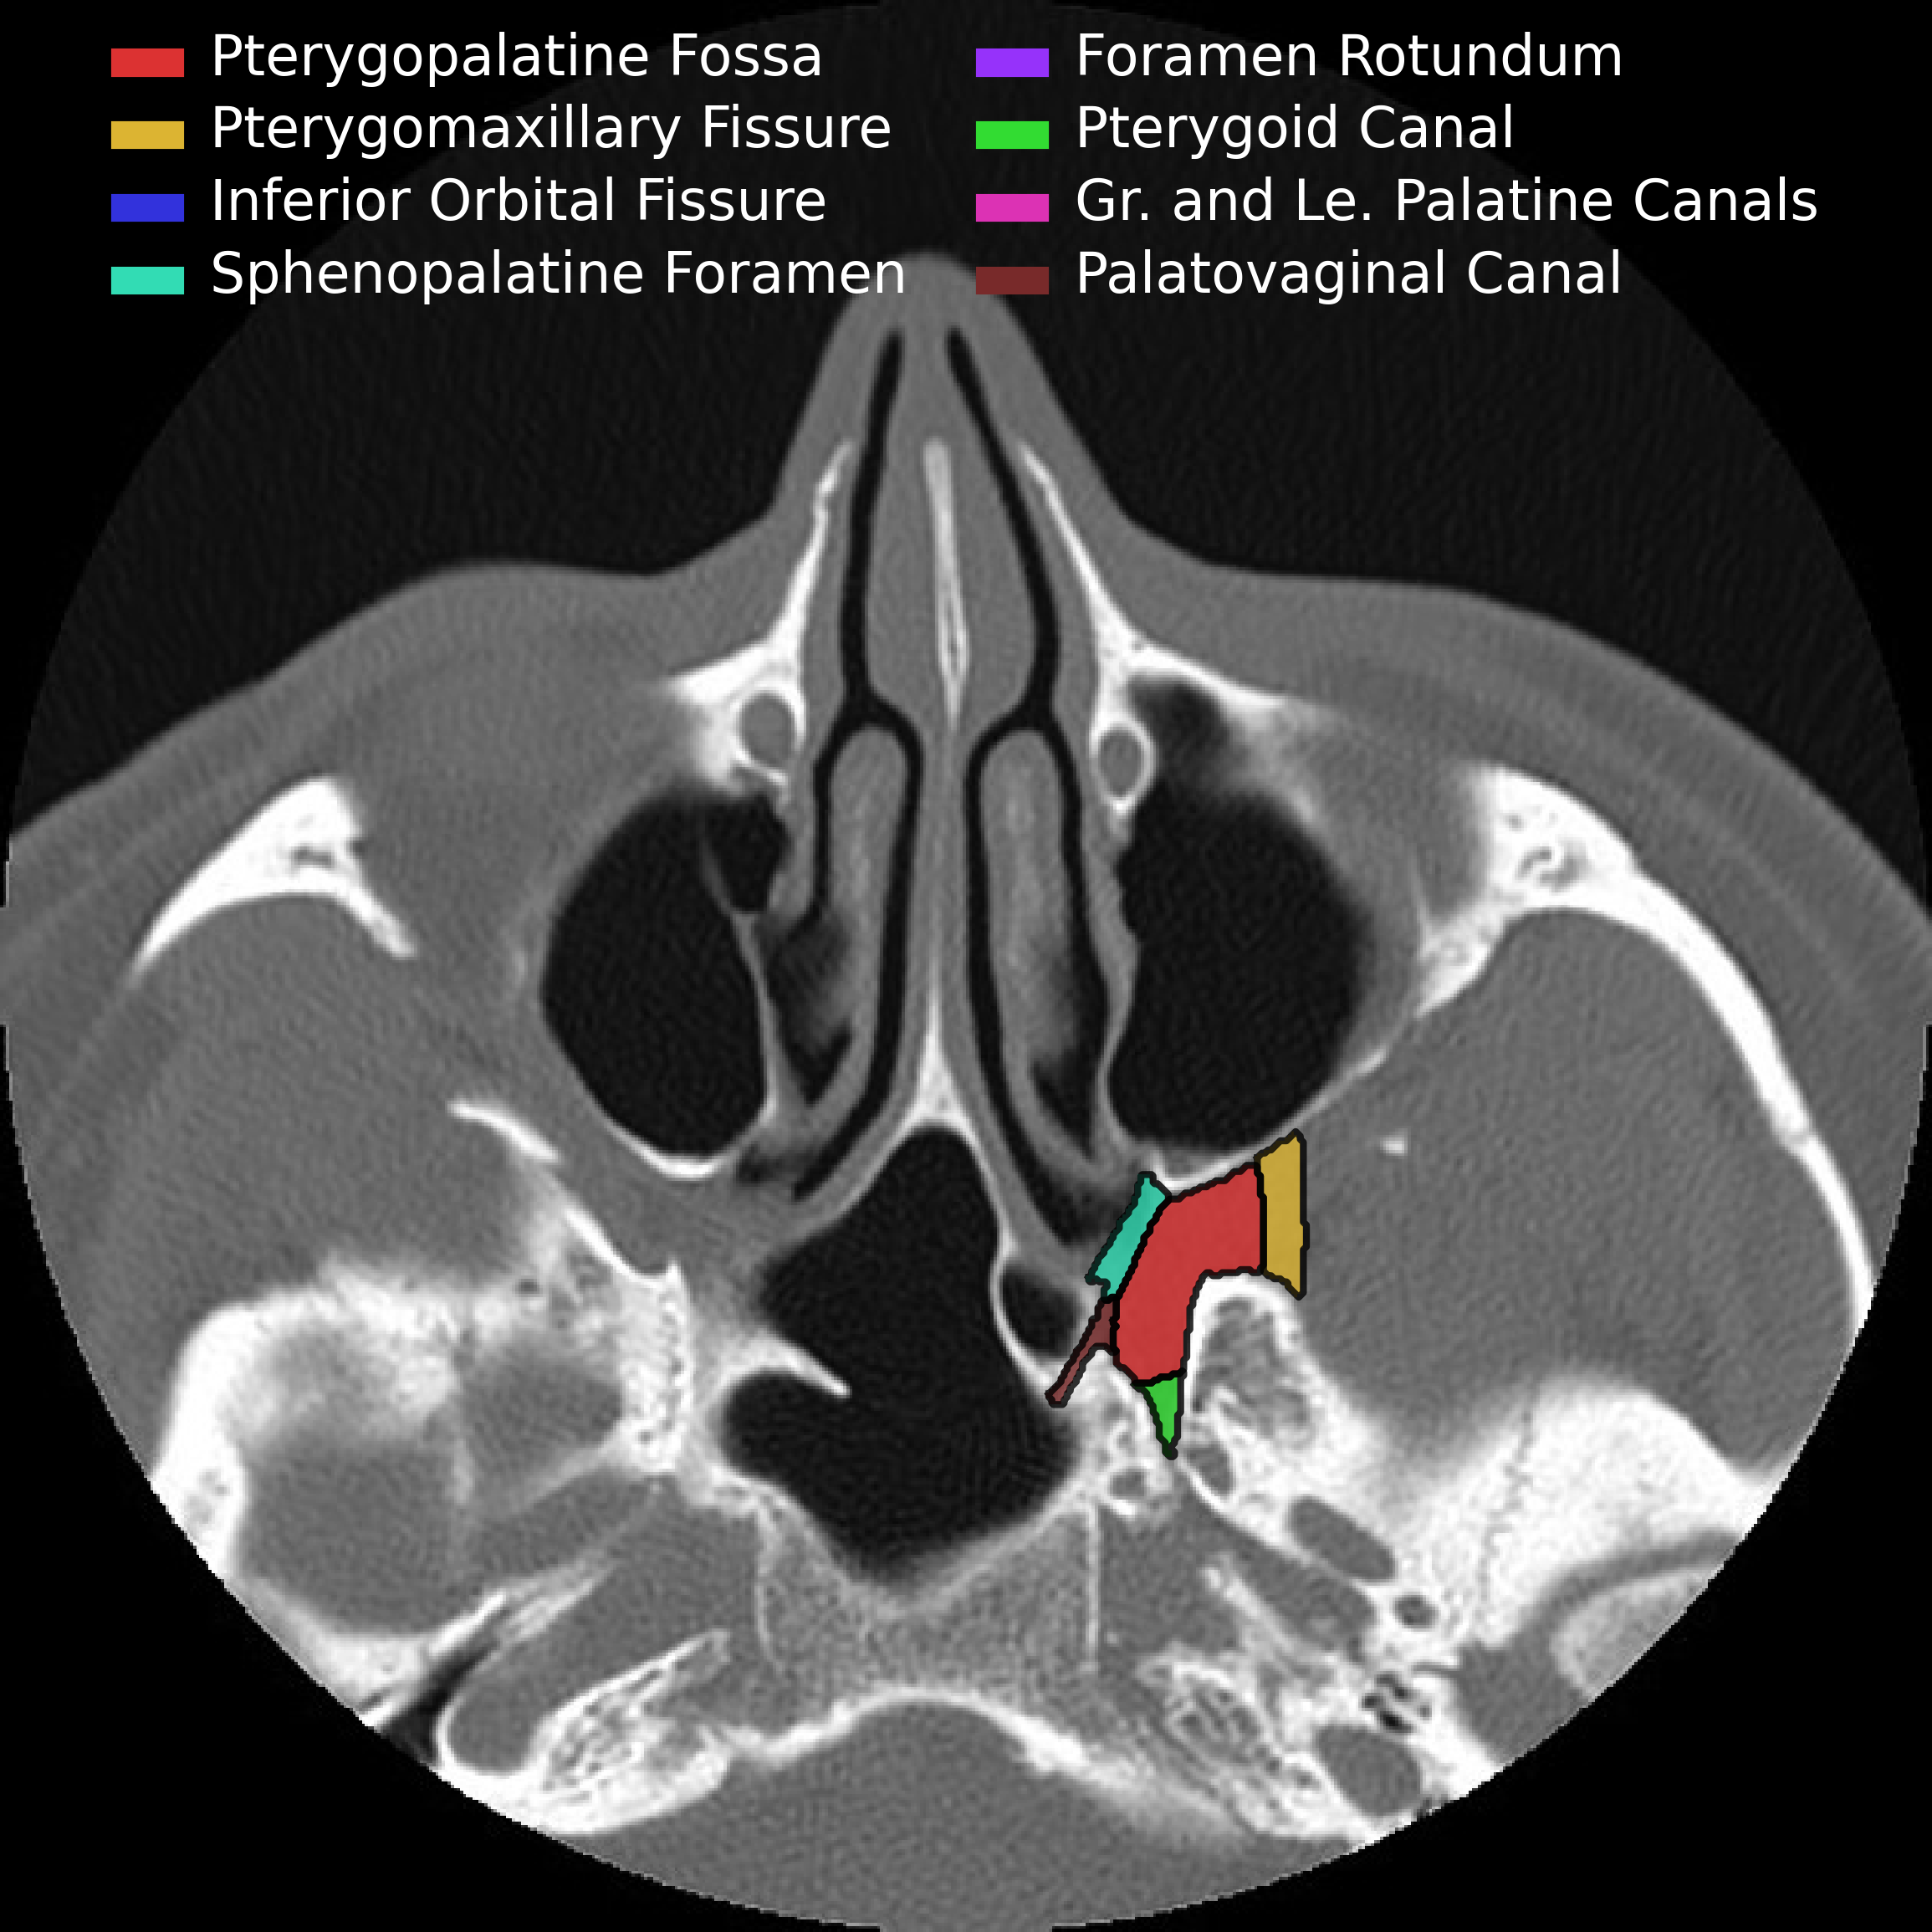

Pterygopalatine Fossa

• Should think of pterygopalatine fossa as one of the major intersections of the face/skull

• Contents:

• Pterygopalatine ganglion

• Terminal aspect of Maxillary artery (& descending palatine artery branch)

• Emissary veins

• Maxillary division of CN V, via foramen rotundum

• Pterygoid canal nerve

The following pictures are a fantastic way to visualize the borders rather than just memorizing them which is a sure fire way to forget them by tomorrow.

• Anterior & Superior - communicates with inferior orbital fissure

• Inferior - Greater & lesser palatine canals

• Communicates with palate

• Lateral - Pterygomaxillary fissure

• Communicates with masticator space

• Medial communication - Sphenopalatine foramen & Palatine bone

• Communicates with nasal cavity

• Transmits

• Sphenopalatine artery

• Posterior superior nasal nerves & nasopalatine nerve

• Posterior

• Posterior-medial - Palatovaginal canal

• Communicates with nasopharynx

• Transmits pharyngeal nerve and pharyngeal branch of maxillary artery

• Posterior-superior - Foramen rotundum

• communicates with Meckel cave & Cavernous sinus

• Posterior-inferior - pterygoid canal (aka vidian canal)

• Communicates with middle cranial fossa

• Transmits vidian nerve, artery and vein

• Important space because allows spread of malignany